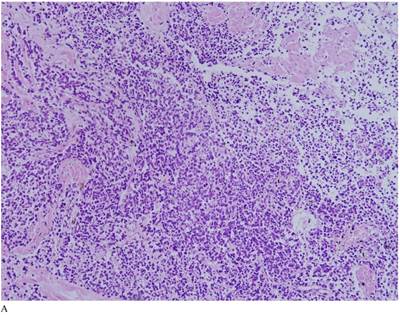

Case 1. A 79-year-old patient with a history of slowly increasing serum PSA levels for 2 years presented to the hospital with a 3-day history of fever. The patient's serum PSA level was 18.12ng/mL (normal <4ng/mL). Digital rectal examination (DRE) indicated grade III prostate enlargement. Magnetic resonance imaging (MRI) showed prostate cancer combined with right seminal vesicle invasion, pelvic lymph node, multi-bone, and liver metastases. An ultrasound-guided prostate biopsy was performed. Pathological examination suggested acinar adenocarcinoma. Gleason scores were 3+4=7. The patient was treated only with endocrine therapy because of his poor general condition. The patient died of respiratory failure caused by multiple metastases of the prostate cancer to both lungs 2 months later. Autopsy pathology revealed mixed SmCC of the prostate, combined with bilateral lung, liver, bilateral adrenal gland, pancreas, bone, and lymph node metastases. The prostate cancer was classified as SmCC with a mixture of acinar adenocarcinoma (Fig. 1A). All metastatic cancers were determined as pure SmCC without component of the acinar adenocarcinoma (Fig. 1B, 1C, 1D).

Case 1. Mixed SmCC. (A) Components of SmCC. (B) Components of acinar adenocarcinoma. Gleason scores were 3+3=6 combined with bilateral lung (C) and liver (D) metastases.

Two of our three cases of SmCC were mixed with acinar adenocarcinoma, and one was pure SmCC. Of the 26 cases in the literature reports, 21 cases were pure SmCC. Under the microscope SmCC tissues were flaky and in a nest-like distribution. Coagulative necrosis was also observed. The cells were small, like oat grains, with one end pointed and the other rounded. The cells contained only a small amount of cytoplasm, with the nuclei bared and darkly colored, and the nucleolus obscured; mitotic figures were frequently seen. For most cases, positive immunohistochemical staining for neurone-specific enolase (NSE), CD56, Syn, and CgA were detected, and immunohistochemical staining was positive for CK, producing a dot-like pattern. Local invasion, lymphatic vessel involvment, and distant metastases were found in 12 (46.2%), eight (30.8%), and nine cases (34.6%) respectively.

The confirmation of SmCC of the prostate relies mainly on pathological findings. Microscopically, SmCC cells are consistently round or short-spindle-shaped, arranged in a flaky or nest-like pattern. The cells only contain a small amount of cytoplasm, with the nuclei bared and darkly colored. The nucleolus is obscured and mitotic figures are frequently observed. Necrosis is also common. Immunohistochemical staining of SmCC cells for NSE, Syn, CgA, and CD56 is usually carried out for diagnosis [24]. Combined use of these four markers often results in a definitive diagnosis. Moreover, PSA, PAP, and P504S expression are rare in SmCC [8] and a CK-positive staining pattern in SmCC is characteristically dot-like. This can be used to differentiate SmCC from the poorly differentiated acinar adenocarcinoma.